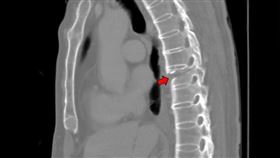

腹痛3個月慘罹大腸癌 醫:差點塞住腸道

父駝背子下背痛 竟都「這疾病」所致